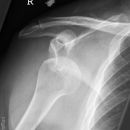

Dislozierte subcapitale Fraktur mit Tbc majus